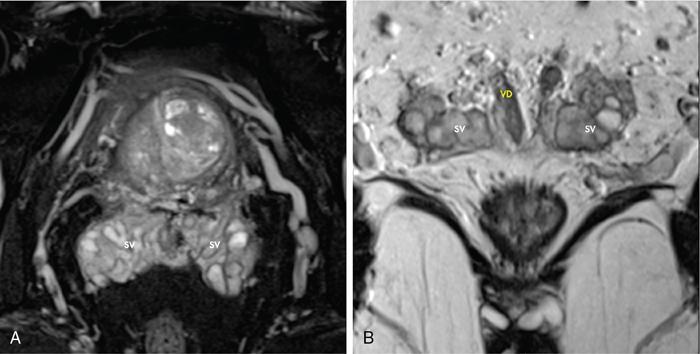

Karthik Ganesan, Disha Lokhandwala, Ujjwal Bhure, Jay Mehta Morphogenesis of the male genitourinary system is governed by the coherent interaction of three units, namely the Wolffian duct, urogenital sinus and foetal gonads. The Wolffian ducts are the embryonic precursors of the male internal genitalia, arising in the anterior intermediate mesoderm at 4 weeks of gestation. They elongate as a cord of cells that caudally extend to the urogenital sinus. Between 5 and 8 weeks of gestation, the urorectal septum divides the cloaca into a ventral compartment, which forms the urogenital sinus, and a dorsal compartment, which forms the rectum. The gonads form as epithelial thickenings on the ventromedial surface of the mesonephros and produce testosterone at 8 weeks of gestation, reaching a peak at 10–15 weeks. Under the effect of testosterone produced by the foetal testis, the prostate anlage forms at the tenth week of gestation. Precursor of the anlage begins with proliferation of solid epithelial buds from the epithelium of the urogenital septum into the adjoining mesenchyme in response to interaction of 5α-dihydrotestosterone with mesenchymal androgen receptors. As growth progresses, solid cords of epithelial cells are formed, growing into the mesenchyme in a specific three-dimensional arrangement (establishes the lobar divisions of the prostate gland). These solid cords develop a central lumen at birth and are lined by a layer of flat basal epithelium and a luminal layer of tall columnar secretory epithelium. Mesenchymal component forms the stroma, which has a large proportion of smooth muscle. Postnatally, the epithelial cords continue to arborize till puberty without any change in volume or glandular architecture. Although the foetal prostate has been described to have a histologically distinct peripheral zone (PZ) as early as 12 weeks of gestation, the mature zonal anatomy develops in concordance with the androgen surge at puberty. The most commonly utilized ultrasonographic technique for the evaluation of the prostate is via a suprapubic approach. The abdominal transducers used in this approach are relatively low frequency and while it offers the advantage of greater depth of penetration without intracavitary probe insertion; however, it does not depict the zonal anatomy and its chief application lies in volume estimation. Hence, transrectal ultrasonography (TRUS) completely outweighs the transabdominal approach in terms of depicting zonal anatomy, visualizing and localizing small lesions, demonstrating vascularity and performing biopsies. TRUS is performed using high frequency transducers (5–7.5 MHz) to optimize soft tissue resolution. An enema is administered 1 h prior to the examination to clear the field of insonation. Patient is positioned in left lateral decubitus, with knees bent toward the chest and ideally a digital rectal examination (DRE) is conducted prior to probe insertion. The transducer is first draped with a sterile barrier and lubricated, After insertion, the barrier is filled with 40–50 cc of water, making sure that no air enters. On completion, water is aspirated and the probe is withdrawn. The gland is initially scanned in the axial plane from the base to the apex, beginning at the level of the seminal vesicles, and the probe is gradually withdrawn to view the entire glandular parenchyma in axial sections up to its caudal aspect. This approach allows a cursory evaluation of glandular symmetry as both halves of the prostate can be evaluated simultaneously. Subsequently, sagittal views are acquired by rotating the probe across the transverse span of the gland, demonstrating the seminal vesicles, midline gland (visualizing both the apex and the base), with sequential scanning up to the contralateral margin of the gland. Sonographically, the prostatic capsule is seen as a smooth well-delineated, hyperechoic structure. With the newer ultrasound systems, the zonal anatomy can be delineated by TRUS; PZ appears echogenic relative to the central zone (CZ) and the transition zone (TZ), which are hypoechoic in juxtaposition (Fig. 11.12.1). Anterolaterally, the preprostatic venous plexuses are seen as anechoic tubular structures with intervening echogenic preprostatic fatty tissue. Glandular volume is estimated using an ellipsoid formula by obtaining the maximum anteroposterior, superoinferior and transverse dimensions and multiplying their product by π/6. Colour Doppler imaging is utilized to illustrate vascularity, as majority of the normal prostatic tissue (excluding the neurovascular bundles [NVBs] and pericapsular and periurethral regions) has symmetrical but sparse flow and an increased microvessel density raises the suspicion of prostatic carcinoma. However, the appearances of prostatic carcinoma can be variable on colour Doppler imaging, ranging from focal increase in vascularity around a nodule to an asymmetric increase in size and number of vessels on the affected side and conventional Doppler has found to elevate specificity by about 5%–10%. Additionally, Doppler imaging has also demonstrated some utility in distinguishing fibrotic tissue from local recurrence. However, vessels supplying cancerous tissue are of the order of 10–50 μm, which is well below the 1-mm resolution limit of conventional Doppler techniques. Contrast-enhanced colour Doppler imaging overcomes this limitation and facilitates imaging of microvessels, using intravenously administered microbubbles (less than 10 μm diameter) of an inert gas (sulphur hexafluoride) with a lipid or galactose shell, allowing quantification of blood flow in the cancerous microvessels. Additionally, these microbubbles act as vascular tracers and by monitoring the passage of a bolus injection through the tissue of interest, time–intensity curves are created. This permits the formulation of functional indices, including bolus arrival time, time to peak intensity, area under the curve and wash-in/wash-out curves. These indices can further extrapolate functional images, on a pixel-by-pixel basis, overlaid on grey-scale images. Quantitative methods to demonstrate perfusion are based on the destruction of microbubbles by high-power ultrasound pulses, and then observing the rate of microbubble replenishment in the field of interest to calculate flow rate. Halpern et al. utilized contrast-enhanced ultrasound and intermittent harmonic imaging with power Doppler, and exhibited an increment in sensitivity from 38% to 65% with a specificity of 80% in prostate cancer detection. Cadence contrast pulse sequencing (CPS) is a low-power multipulse imaging technique utilizing pulses with variable amplitudes and phases followed by a summation of the resulting echoes, permitting tissue suppression, allowing detection of even a small amount of contrast agents retained in the tissues. Real time elastosonography evaluates and quantifies tissue stiffness (Young’s modulus) by measuring strain under an applied stress (transducer compression) and maps areas of variable stiffness in colour-coded and grey-scale images simultaneously and shows potential in improving prostatic carcinoma detection. In a study comparing elastography and T2-weighted (T2-w) endorectal magnetic resonance imaging (MRI), similar sensitivity rates and negative predictive values (NPVs) were attained in the detection of prostatic carcinoma. Prostate gland is an inverted cone-shaped subperitoneal retropubic gland, with its base located rostrally and apex located caudally. The base is attached to the bladder neck and the apex sits on the urogenital diaphragm and abuts the medial surface of the levator ani muscles, namely the pubourethralis portion, which is separated from the inferolateral surfaces of the gland on either side by the prostatic venous plexus. Normal prostate gland measures approximately 4 × 3 × 3 cm, 15–20 g in weight, with a median volume of 11.5 mL (range, 1.6–20.6) in patients between 21 and 25 years and a median volume of 39.6 mL (range, 13–169.8) in patients between 38 and 83 years. The first comprehensive publication describing the anatomical subdivision of the prostate gland was in 1912 by Lowsley, based entirely on the embryonic glandular morphology at a series of gestational age groups. The budding prostatic ducts were seen to proliferate in five distinct clusters from the primitive urogenital sinus, which formed the basis of its lobar subdivision. It was divided into a ventral lobe (anterior to the urethra), two lateral lobes (lateral to the ejaculatory ducts), a posterior lobe (between the ejaculatory ducts) and a middle lobe (above the ejaculatory ducts). This classification had several shortcomings, the foremost being inclusion of only the embryonic prostate during its conception. Frank highlighted these aspects in 1953 and stated that no definite lobar boundaries exist in the adult prostate and further criticized the exclusion of periurethral glands (inner gland), identifying them as the sole site of origin of benign prostatic hyperplasia (BPH). The chief drawback of all research prior to 1968 was the lack of a concrete histological basis to support the seemingly arbitrary subdivision. McNeal was the first to ascertain histological heterogeneity within the glandular tissue and used it as the basis of his well-acclaimed prostatic zonal classification. The zonal anatomy of the prostate gland conceived by McNeal divided the gland into four distinct zones, namely the TZ, PZ, anterior fibromuscular zone (AFMZ) and the CZ (Fig. 11.12.2). McNeal used the plane of the distal urethra to describe the zonal relationships and divide the gland broadly into three parts, namely the base, midgland and the apex (Fig. 11.12.3). The improved understanding of the prostate anatomy coincided with the development of MRI in the late 1980s, which could depict the zonal anatomy, unlike ultrasonography (USG) or computed tomography (CT). Patterns of ductal growth and radiation from the prostatic urethra form the basis of the zonal anatomy of the gland. Ducts arising from the proximal urethral segment grow towards the urinary bladder. Tiny ducts which are confined by the preprostatic sphincter form the small periurethral gland, whereas ducts which develop distal to the lower border of the preprostatic sphincter extend laterally and then anteromedially to form the TZ. Ducts arising from the verumontanum in the vicinity of the ejaculatory duct orifices and are directed towards the base along the course of the ejaculatory ducts form the CZ, whereas ducts which arise from the lateral recess of the posterior urethral wall of the verumontanum and distal urethra radiate laterally to form the PZ and rostrally posterior to the CZ at the base of the gland. PZ is the dominant glandular component of the prostate gland comprising approximately 70% of the glandular tissue. On T2-w images, the normal PZ has a high T2 signal intensity (SI), owing to the abundant ductal and acinar elements with sparsely interwoven smooth muscle, and can broadly divided into three sections as per the sector map in Prostate Imaging Reporting and Data System Version 2.1 (PI-RADS v2.1), namely posterior medial, posterior lateral and anterior sections (Fig. 11.12.4). At the apex, the anterior sections have a horn-like morphology, curving anteromedially, to nearly encircle the urethra and abut the AFMZ. At the midgland level, the PZ comprises the posterior, both lateral and the anterolateral parts of the gland. At the base, the PZ is located posterior and superior to the CZ and TZ. CZ is an ovoid-shaped structure at the base of the gland, comprising approximately 25% of the glandular tissue, with its apex located at the verumontanum, surrounding the ejaculatory ducts. Beyond age 35, volume of the CZ starts to gradually diminish, as well as the CZ is compressed by the enlarged TZ. In the initial MR studies of prostate, the CZ could not be easily delineated from the TZ. Vargas et al. demonstrated in a population with a mean age of 60 years undergoing MR for prostate cancer assessment, the CZ was visible in 81%–84% of patients. Hansford et al. identified the CZ in 92%–93% of patients on T2-w images and 78%–88% of patients on apparent diffusion coefficient (ADC) maps. Histologically, substantial differences exist between the CZ and PZ, which reflect in the differential appearance on T2-w imaging. These differences are probably attributable to the differential origin, as the CZ is derived from the Wolffian duct, and the PZ and TZ are derived from the urogenital sinus. In the CZ, the acini appear larger and more irregular, with numerous epithelial covered ridges or septa project from the walls of the acini into the lumen, forming a characteristic Roman bridge architecture and intraglandular lacuna, with a prominent basal layer, crowded epithelial cells with granular eosinophilic cytoplasm, decreased luminal fluid and compact stroma. PI-RADS v2 has discouraged the use of the term central gland, as it is not reflective of zonal anatomy or reported on pathologic specimens. CZ demonstrates homogeneously low signal on the T2-w images and ADC maps and can, therefore, mimic prostate cancers. CZ is best identified on the coronal plane T2-w images paralleling the plane of the distal urethra, and appears as a symmetric paramedic paired structures surrounding the ejaculatory ducts from the base of the gland to the verumontanum (Fig. 11.12.5). TZ comprises approximately 5% of the glandular tissue of the prostate. On T2-w images, the TZ normally appears as a homogeneously hypointense structure surrounding the proximal urethra at the base and the midgland level; however, it can also demonstrate inconsistent SI, depending on the relative proportion of glandular and stromal elements (Fig. 11.12.6). Glandular hyperplasia produces higher SI (dominance of acinar elements and secretions), while stromal hyperplasia exhibits lower SI (dominance of muscular and fibrous elements). The TZ is easily demarcated from the PZ by a thick homogeneously low T2 signal surgical capsule, which becomes pronounced in BPH. With increasing age, the TZ demonstrates variegated signal on the T2-w images and ADC maps, due to differential growth of the stromal and glandular elements. AFMZ is a nonglandular muscular tissue that drapes the anterior surface of the gland, superiorly blending into the smooth muscles of the bladder neck and inferiorly extending to the prostatic urethra at the glandular apex. AFMZ is comprised of smooth muscles, which blends with the smooth muscle fibres surrounding the urethra, and rostrally merges with the bladder neck and preprostatic sphincter. High smooth muscle content of the AFMZ is responsible for the MR signature, where in it appears markedly hypointense on the T2-w images and ADC maps, and hypoenhances on the multiphase contrast series (Fig. 11.12.7). With the advancing age, temporal reduction in the size of the AFMZ is noted due to the compressive effects of the BPH. Capsule surrounds the prostate gland, anteriorly merging with the AFMZ anteriorly. Two discrete defects are identified in the prostate capsule, at the base of gland where the ejaculatory ducts enter the prostate and at the apex where in the stroma blends with the sphincter. The capsule is perforated along the anterolateral aspect by multiple vessels and nerves. The capsule appears as a thin dark rim surrounding the gland on the T2-w images and may reveal delayed enhancement on the postcontrast images (Fig. 11.12.8). Primary goal of radical prostatectomy (RP) is to achieve oncologic efficacy, both in terms of short-term and long-term clinical outcomes. However, as the majority of prostate cancers have an indolent clinical course, preservation of function in terms of continence and potency is equally important, and the key to this is a keen understanding of the fascial anatomy and neuroanatomy of the prostate gland. Fascial anatomy of the prostate gland is anatomically complex and poorly understood, and a thorough understanding of the interfacial planes is crucial to avoid mechanical or thermal injury to the NVBs. Periprostatic fascia comprises of a condensation of layers of connective tissue that encapsulate the gland and suspend it from anterior pelvic wall via puboprostatic ligaments. Laterally, the visceral and parietal endopelvic fascial layers fuse to form the fascial tendinous arch. Periprostatic fascia covers the prostate gland and capsule, comprises of two fascial layers, including an inner layer (prostatic fascia) and an outer layer (levator ani fascia), with thin interfascial planes separating these fascia from one another and the prostate capsule. Posteriorly, a continuous fascial layer known as Denonvilliers’ fascia covers the prostate and seminal vesicles. Distribution of periprostatic nerves is highly variable, with growing evidence of nerves both along the dorsolateral and ventrolateral surfaces of the prostate gland. Most of the periprostatic nerves are found posterolaterally; however, a significant portion of the nerves are located ventrally as seen by Eichelberg et al. (21.5%–28.5%) and Lee et al. (19.9%–22.8%). Although anatomic studies have confirmed the presence of ventrolateral periprostatic nerves, the exact clinical importance and functionality of these nerve fibres has not been proven. The cavernous nerves are situated posterolaterally and are the basis of nerve-sparing RP procedure proposed by Walsh and Donker. Unlike the initial theory of Walsh and Donker, few papers have proposed that the nerves are diffusely scattered along the surface of the gland in the form of a curtain or spray-like arrangement without clear bundle formation. Kourambas et al. assessed the precise relationship of the NVBs and cavernous nerves to Denonvilliers’ fascia and proposed that the nerves were not restricted posterolaterally, but were rather diffusely scattered within the fascia extending up to the midline (Lunacek et al., Takenaka et al.). On the basis of more diffuse arrangement of the periprostatic nerves, surgical techniques have been modified, resulting in a more anterior dissection called the ‘curtain dissection technique’ or alternatively a ‘superveil’ technique to preserve the NVBs within the lateral prostatic fascia. The NVB lies within areolar connective tissue surrounding the gland, which separates the capsule from the periprostatic fascia and provides a plane of dissection during nerve-sparing prostatectomy. Prostate gland is supplied and drained by periprostatic vessels, which also supply and drain the penis. Arterial supply of the gland is highly variable and is typically from branches of the internal pudendal artery, which course inferior to the gland prior to supplying the penile cavernosal tissue. Off late, these vessels have gained prominence in radiation-induced erectile dysfunction (ED) (potential vasculopathy), which have led to the development of newer vessel-sparing radiotherapy techniques. Further, with the advent of prostate arterial embolization in benign prostatic hypertrophy (BPH), the vascular supply of the gland is becoming increasingly vital to understand. Gland drains into the obturator, internal iliac, external iliac, common iliac and presacral lymph nodes. Dorsal venous complex is identified immediately ventral to the gland and also drains the penis. Periprostatic nodes are uncommon, are usually discovered near the base of the gland, and are only occasionally seen on MRI. Urethra is the principal anatomic reference point in the prostate gland. Urethra can be divided into a proximal segment and a distal segment, the point of differentiation being located at the verumontanum wherein the urethra makes an approximately 35-degree angulation. The angulation is highly variable and is further affected by the growth of the TZ. On MRI, the distal segment is more conspicuous vis-à-vis the proximal segment and appears a hyperintense core surrounded by a low signal rim on T2-w images. Preprostatic sphincter encases the proximal urethra from the base of the gland to the base of the verumontanum and merges with the AFMZ anteriorly. Verumontanum appears hyperintense on the T2-w images, lies within the distal urethral segment, beyond which the distal urethral segment is partially encircled by striated muscles which blend with the external sphincter beyond the apex of the gland. External sphincter is located distal to the apex is incomplete posteriorly and is anchored into the PZ and surrounds the membranous urethra. Damage to the external sphincter during RP or transurethral resection of the prostate (TURP) may lead to urinary incontinence. Seminal vesicles are paired structures identified posterosuperior to the base of the prostate gland, which appear as convoluted fluid-filled structures. Due to the high fluid content within the normal seminal vesicles, these structures appear as paired structures with intermediate signal walls surrounding a hyperintense core on T2-w images (Fig. 11.12.9). Vas deferens are paired structures located rostral to the base of the gland and anteromedial to the seminal vesicles and appear as cord-like structures with variable signal on the T2-w images. Duct of the seminal vesicle and vas deferens unite in the posterior aspect of the base of the gland to form the ejaculatory duct, which courses caudally to the verumontanum along the plane of the distal urethra, and drain into the orifices in the midconvexity of the verumontanum. Prostate-specific antigen (PSA) is a serine protease, secreted by epithelial cells of the prostate gland and has been found in normal, benign and malignant prostatic tissues. Traces of PSA have also been isolated from endometrial tissue, breast tissue, adrenal neoplasms and renal cell carcinomas; however, for all clinical purposes, PSA is considered as an organ-specific biomarker. Papsidero first demonstrated and quantified serum PSA, which steered the epoch of prostate cancer screening and early detection of prostatic carcinoma. Subsequent studies showed that PSA screening often led to overdiagnosis of low-grade prostate cancers, with no survival difference between the PSA screened and nonscreened groups. Additionally, PSA levels were found to be elevated in a spectrum of prostatic pathologies apart from carcinoma, including prostatitis and benign hyperplasia. The likelihood of overdiagnosis coupled with the lack of specificity set grounds for the longstanding PSA controversy. Did the benefits of screening outweigh the risks of overtreatment? To elevate the specificity of serum PSA testing, a plethora of indices were devised, including free PSA and total PSA, free-to-total PSA (f/t PSA) ratio, age-specific PSA, PSA velocity (PSA-V) and PSA density (PSAD). Serum PSA exists in three forms; the major form (approximately 75%) is bound to alpha-1-antichymotrypsin, followed by free PSA (constituting 5%–50% of serum PSA). The third form (PSA bound to alpha-2-macroglobulin) is not clinically relevant and cannot be detected by any commercial test. A study by Stenman et al. established that a higher proportion of bound PSA and hence a lower ratio of f/t PSA is associated with prostate cancer. Conversely, free PSA can be utilized during follow-up for men with an initial negative biopsy result, wherein declining free PSA with a persistently elevated total PSA would raise suspicion of a neoplastic aetiology. As per the ACS guidelines (Table 11.12.1) for early detection of prostate cancer, men with a 10-year life expectancy or higher should have the opportunity to make an informed (regarding benefits, risks and uncertainties associated with PSA screening) decision for serum PSA testing, with or without DRE. For those who choose to undergo PSA screening, subsequent screening interval is determined on the basis of baseline PSA value. For values below 2.5 ng/mL, screening interval can be extended to 2 years and for PSA between 2.5 ng/mL and 4 ng/mL, an individualized approach is adopted following risk assessment to recommend either further referral or screening on a yearly basis. A PSA level of 4 ng/mL or higher warrants referral for further evaluation or biopsy, for men at average risk for prostate cancer. Although age-specific PSA (Table 11.12.2) is not a component of the ACS guidelines, it is considered as a beneficial parameter in determining the need for biopsy. As there is an expected rise in PSA values with age, setting a lower cut-off value for younger men would increase the sensitivity of detecting organ confined cancers and a higher value in older men would increase specificity. aThere is no proven rationale for using a single PSA-V threshold value. PSA screening guidelines for treated localized prostate cancers are variable and the definition of biochemical (PSA) recurrence remains debatable. Due to this inconsistency, the Prostate Cancer Guidelines Update Panel recommended a standard definition for biochemical recurrence (BCR) after RP and set a cut-off serum PSA (acquired between 6 weeks and 3 months of surgery) of 0.2 ng/mL or greater, along with a second confirmatory PSA. While there is a significant fall in PSA values after RP and a single raised PSA is sufficient to raise suspicion of recurrence, postradiotherapy recurrence requires a rising trend rather than a single cut-off value. The ASTRO Consensus Panel defined postradiotherapy prostate cancer recurrence as three consecutive raises in PSA values after a baseline has been reached. A hiatus in this definition was that no specific time interval between consecutive increases in PSA was determined. In addition to its utility as a screening tool, PSA is also a good prognosticator when used in conjunction with biopsy Gleason score and clinical T-stage, and several pretreatment prostate cancer risk stratification systems are based on these indices. D’Amico et al. proposed a three-group risk stratification system in 1998, which categorized nonmetastatic (M0) carcinomas as low risk, intermediate risk and high risk. Low-risk prostate cancer was defined as 1992 AJCC T1/T2a, PSA ≤10 ng/mL and Gleason score ≤6. Intermediate-risk prostate cancer was defined as 1992 AJCC T2b, and/or PSA 10–20 ng/mL and/or Gleason 7 disease. High-risk disease included any one of the following: 1992 AJCC ≥T2c, PSA >20 ng/mL or Gleason 8–10 disease. In 2001, the GUROC published the results of a consensus meeting which categorized the groups as follows: low risk – 1997 AJCC T1–T2a, PSA ≤10 ng/mL and Gleason ≤6; intermediate risk – 1997 AJCC T1–T2, PSA ≤20 ng/mL and Gleason ≤7 not otherwise low risk and high risk – 1997 AJCC T3–T4 or PSA >20 ng/mL or Gleason 8–10. In due course, newer classification systems have been developed (Table 11.12.3), including the National Comprehensive Cancer Network (NCCN, USA), National Institute for Health and Clinical Excellence (NICE, UK), European Society of Medical Oncology (ESMO), American Urological Association (AUA) and the European Association of Urology (EAU). The NCCN guidelines also incorporate very low-risk (T1c, and Gleason score ≤6, PSA ≤10 ng/mL, <3 positive biopsy cores each ≤50% involved and PSAD of <0.15 ng/mL/g) and very high-risk (T3b–T4) categories. AUA, American Urological Association; EAU, European Association of Urology; GUROC, Genitourinary Radiation Oncologists of Canada; NICE, National Institute for Health and Clinical Excellence; CAPSURE, Cancer of the Prostate Strategic Urologic Research Endeavour; NCCN, National Comprehensive Cancer Network; ESMO, European Association of Urology; T, T-stage; GS, Gleason score; PSA, prostate-specific antigen. Note: Use of the 1997 TNM staging system (T2a one lobe involvement, T2b two lobes involvement, no T2c category). PSA, DRE and TRUS form the diagnostic triad for prostatic carcinoma. It has been well established that manipulations of the prostate gland, including prostatic massage, cystoscopy and perineal biopsy cause a potential increase in serum PSA levels. This raised the question of TRUS affecting PSA levels and it was found to cause a very small rise in PSA only in patients with prostatitis. The effect of DRE on serum PSA levels is also controversial, while some studies found a transient increase in PSA, others found no significant rise in PSA levels after DRE. Therefore, it is advisable to obtain blood samples for PSA testing either prior to DRE and TRUS or after at least 7 days. PSA-V refers to the change in PSA over time using serial measurements. Ideally, at least three consecutive measurements over at least 18–24 months should be used. Carter et al. first defined PSA-V and found that a value of 0.75 ng/mL per year or greater was indicative of carcinoma with a high sensitivity and specificity. Consequently, several studies disproved a definite relationship between PSA-V and prostate cancer, stating that there was no rationale behind a single threshold value for PSA-V. Further, it was found that calculating PSA-V was arduous and while elevated PSA values on serial examinations should raise alarm, there was no added benefit of formally calculating PSA-V. As per NCCN guidelines, the PSA-V cut-off should be based on the initial PSA value with a PSA-V of 0.35 ng/mL/y, when the PSA is ≤2.5 ng/mL and 0.75 ng/mL/y, when the PSA is 4–10 ng/mL PSAD was developed in order to correlate prostate volume and PSA values. The basis of PSAD was that cancer cells produce more PSA per unit volume than normal cells. It is calculated as PSA value divided by the prostate volume as determined by TRUS. This reliance on TRUS leads to interobserver variability and hence PSAD values would differ with the performing sonologist. The chief utility of PSAD is in the diagnostic grey zone of PSA values between 4 and 10 ng/mL and the most commonly used cut-off value is 0.15 ng/mL/cc. However, more recent studies have shown that a value of 0.08 ng/mL/cc has an NPV of 95% in predicting prostate cancer. Additionally, PSAD in conjunction with MRI (PI-RADS score) has proved to be a reliable prognosticator for Gleason score upgrading. The most significant application being avoiding unnecessary biopsies as PI-RADS scores of 1–3 along with PSAD values <0.15 ng/mL/cc showed no Gleason score upgrading on repeat biopsies. In summary, most guidelines recommend shared decision-making for screening of prostate cancer. Limited testing should be conducted in men with low PSA values and a lower life expectancy. The aim should be to overcome challenges posed by the inherent nonspecific nature of serum PSA and reduce superfluous testing, unwarranted biopsies and overdiagnosis. Reliance on parameters like PSA-V that do not have a proven scientific basis is avoidable. Whereas applications of PSA like PSAD along with MRI can greatly reduce patient burden by avoiding follow-up biopsies. Lastly, PSA has no role in assignment of a PI-RADS category, which is based on multiparametric MRI (mpMRI) findings alone. Several ‘novel biomarkers’ are now being developed which are more specific in detecting high-grade prostatic carcinomas. Other human kallikrein proteins have been identified, as prostate cancer biomarkers, of which, human kallikrein 2 (hK2) has shown a high specificity. While hK2 and PSA have an overlapping primary structure, malignant cells express hK2 to a higher degree than benign epithelial cells, particularly in aggressive cancers. Engrailed-2 (EN2) is an HOX gene family transcription factor seen exclusively in malignant prostate tissue, with a reported sensitivity and specificity of 66% and 88%, respectively. Annexin A3 is a calcium-binding protein measured in urine samples following prostatic massage, potentially reducing unnecessary biopsy in men with a PSA of 2–10 ng/mL. However, extensive prospective evaluation of these biomarkers is necessary to replace PSA testing in clinical practice. Positron emission tomography (PET)/CT has evolved over the last two decades to make a paradigm shift in the field of imaging, moving from morphological imaging to molecular level and completely changing the approach to how we view the disease. Though the main workhorse tracer in the field of PET/CT is 18-fluorine-fluorodeoxyglucose (18F-FDG), it has limitations with regard to prostate cancer, especially in indolent or well-differentiated ones. However, that void has been filled up by the new kid on the block and that is prostate-specific membrane antigen (PSMA)-based radiotracer. PSMA is a type II transmembrane protein with intracellular (19 amino acids), transmembrane (24 amino acids) and extracellular (707 amino acids) domains, which functions biochemically as a glutamate carboxypeptidase. After a ligand binds to PSMA, internalization occurs and it is either retained in lysosomal compartments or released into the cytoplasm. PSMA expression and localization in the normal human prostate is associated with cytoplasm and apical side of the epithelium surrounding prostatic ducts but not basal epithelium and neuroendocrine or stromal cells. Neoplastic transformation of prostate tissue results in the transfer of PSMA from the apical membrane to the luminal surface of the ducts. PSMA is an ideal target for molecular imaging of prostate cancer as its expression is significantly upregulated in prostatic carcinoma cells compared to benign prostatic tissue, in density (100 to 1000 times) as well as activity (8 to 10 times). PSMA expression increases with increase in Gleason score, stage and grade of tumour, with further increased expression with transition to androgen-independent/castration-resistant prostate cancer. PSMA-binding analogues, because of their high sensitivity and specificity, possess precise imaging characteristics required for critical decisions in the management of prostate cancer (PCa). The most commonly used PSMA radiotracer is 68Gallium-PSMA-11, followed by 18F-PSMA. The availability of 18F-labelled PSMA radiopharmaceutical has helped to advance the reach of PSMA PET imaging to wider locations owing to higher available amount of the radiotracer due to its production from a cyclotron, compared to 68Ga-PSMA which is eluted from individual in-house generator. Additional benefit is accrued with excellent image quality owing to optimized radiotracer doses, higher imaging statistics and favourable decay properties of 18F radioisotope. The normal physiological biodistribution of PSMA-based radiotracers is seen in lacrimal and salivary glands, liver, spleen, kidneys and intestine. Physiological activity is also seen in celiac and cervicothoracic ganglia. Unbound PSMA radiotracer is excreted by the kidneys into the urinary bladder. PSMA PET/CT has established roles of varying degrees in the imaging of different aspects of prostate cancer including primary diagnosis, staging, BCR after primary prostate cancer treatment (prostatectomy), identification and significance of oligometastasis, restaging and treatment response assessment and monitoring. PSMA PET/CT is useful at the stage of diagnosis in that subset of patients with tumour-negative biopsy samples, by contributing the useful molecular information to mpMRI, helping to precisely delineate suspicious lesions for targeted biopsies. In intermediate-risk to high-risk primary prostate cancer patients, PSMA-based imaging has shown improvement in detection of metastatic disease compared to the CT and mpMRI, which has led to reduced demand and dependence on additional cross-sectional imaging or bone scintigraphy. Furthermore, PSMA PET/CT has also established its clear advantage over conventional imaging in patients with biochemically recurrent prostate cancer with improved and increased detection of metastatic sites even at low serum PSA values. As it happens in cancer, biopsy is the standard of diagnosis and likewise in PCa, it is the multicore biopsy, which is the gold standard. However, because of its size, location, approach and sensitive and delicate nature, yield and accuracy can often be restricted, especially in inexperienced hands. The diagnostic yield of biopsy can go down as low as 40% and false negative (FN) rate can climb as high as 25%–30%. PSMA overexpression follows high-grade PCa cells and increases with Gleason score. In normal prostate tissue, PSMA to PSA ratio is about 1, which decreases in BPH, increases in primary PCa cells, further increases with intratumoural angiogenesis, higher in metastatic lesions than in primary PCa cells and further upregulated in castration-resistant situation. In a study by Litwin and Tan in 2017, the FN rate of multicore biopsy was around 21%–28% and about 15% of the cases were undergraded vis-à-vis final prostatectomy results. While the diagnostic accuracy of random multicore biopsy was around 76.3%, that of 68Ga-PSMA PET/CT was upward in the range of 85.5%. The role of PSMA PET/CT in the primary/initial diagnosis of prostate cancer is generally limited to clinically intermediate-risk to high-risk patients with negative biopsy or reluctance to biopsy or noncooperation or nonfeasibility and for confirmation and staging in clinically high-risk patients. In low-risk patients, metastatic spread is very unlikely and hence it is a relative indication at the time of initial diagnosis in low-risk patients. And, its role in screening is variable and debatable (Fig. 11.12.10). Staging is crucial as it has considerable influence on deciding further line of management and treatment choices, which includes RP, radiotherapy or palliative systemic treatment, deciding on the extent of the pelvic nodal dissection during surgery, planning the radiotherapy field and consideration of multimodal therapy. Accurate staging helps to make the most appropriate choice of treatment modality (Fig. 11.12.11). In a meta-analysis of five studies with histopathology as gold standard, which included 216 patients, the per-lesion sensitivity of 68Ga-PSMA PET/CT ranged from 33% to 92% (33% value being an outlier due to the retrospective analysis based only on the reports, in absence of the images) with higher specificity of 82%–100%. For T-staging, PSMA PET/CT showed a significantly higher tumour detection rate of 92% vis-à-vis 66% with MR alone. In regard with N-staging, the majority of metastatic nodes from prostate cancer are small subcentimetre-sized, less than 8 mm, which are overlooked, missed or inconclusive on morphological imaging (CT and MRI) (falling below size criteria for morphological imaging). Accurate N-staging is important because lymph node involvement is a critical prognostic factor in cancer management, and precise pelvic nodal clearance could be curative and could make a difference in treatment success and long-term outcome in prostate cancer (Fig. 11.12.12). Also, accurate prediction of pelvic nodal metastases may spare nodal dissection, shorten surgical time and in turn help to reduce undesirable complications. In one study from 2016 involving 130 patients with intermediate-risk to high-risk prostate cancer, the metastatic nodal detection rate by 68Ga-PSMA PET was around 66% compared to 44% with MRI. PSMA PET has shown superior predictive value for surgical response over Gleason score, pT stage and PSA (at the time of imaging). In a literature overview by Luiting et al. in 2019 involving 9 retrospective and 2 prospective studies, the specificity of PSMA PET/CT in detection of pelvic nodal metastases before initial treatment reached as high as 80%–100%. PSMA PET/CT increases the confidence level in the evaluation of nodal metastases and an NPV reaching up to 86%. With imaging becoming more precise and adding different modalities together, the question arises about the tiny nodes less than 5 mm size. In a study by van Leeuwen et al. in 2017, the mean size of missed lymph node metastases was 2.7 mm. In a recent study by Ferraro et al. in 2020, about the impact of PSMA PET staging on clinical decision-making in intermediate-risk to high-risk prostate cancer patients, PSMA PET provided new information in 36% of patients and this helped to change treatment decision in nearly 27% of patients, which means in every fourth patient they studied. PSMA PET in combination with CT or MRI can achieve complete and precise Tumor, Nodes and Metastases (TNM) staging including staging of local tumour, nodal assessment and bone and organ/visceral metastases, in one single imaging session, with improved accuracy and better outcome, and in turn leading to precise treatment planning, eventually superseding conventional imaging. Accurate localization of prostate cancer lesions in patients with BCR is a major challenge. Especially at low serum PSA values (as low as less than 0.5 ng/mL), the precise determination of localized disease and metastatic spread is of great importance for further disease management. Conventional imaging modalities including CT scan or bone scintigraphy have limited detection rate for metastatic disease at low serum PSA values in this setting of BCR. PSMA PET/CT imaging plays a very valuable role in the evaluation of BCR (Fig. 11.12.13), which is indeed very critical and important aspect in prostate cancer management. The international consensus on BCR includes PSA >0.2 ng/mL for two times after prostatectomy, or PSA nadir + 2 ng/mL after radiotherapy or brachytherapy. With the incorporation of PSMA PET/CT in the imaging armamentarium, the overall detection rate for local recurrence as well as metastases with BCR after prostatectomy reached up to 90%. The detection rate increases with rising PSA level, jumping over 90% with PSA level going above 1 ng/mL. In a homogeneous consecutive cohort of 248 patients with BCR after RP with mean serum PSA value of 1.99 ng/mL, studied by Eiber et al., 68Ga-PSMA PET/CT showed detection rates of 57.9%, 72.7%, 93.0% and 96.8% for patients with serum PSA values of 0.2–<0.5 ng/mL, 0.5–<1 ng/mL, 1–<2 ng/mL and ≥2 ng/mL, respectively. Tumour Gleason score or androgen deprivation therapy (ADT) did not significantly influence the detection rates (Fig. 11.12.14). These detection rates for 68Ga-PSMA PET are substantially higher than those reported for choline-based PET radiotracers, which fell between 19% and 36% at serum PSA levels of <1.5 ng/mL. The improved detection rates are due to the incremental value of molecular imaging as 68Ga-PSMA PET exclusively showed findings not evident on diagnostic CT in 32.7% of patients with information about additional involvement of different anatomical region in 24.6%. A high PSA-V and short PSA doubling time showed a tendency towards increased detection rates, though not statistically significant. As salvage radiotherapy is most effective at low serum PSA values, optimized radiotherapy planning with precise definition of target volume for concerned lesions for appropriate boost radiotherapy can be achieved with the help of PSMA PET/CT imaging. Lesion detection rate with PSMA PET/CT in the setting of BCR: PSMA PET/CT imaging helps to identify patients with oligometastatic disease who are suitable for salvage therapy with PSMA-radioguided surgery. PSMA radioligands, by the virtue of their high sensitivity and specificity, can be used for intraoperative tracking of even small metastatic prostate cancer lesions that can be well localized and subsequently removed using this radioguided surgery for salvage procedures. Identification and treatment of oligometastatic disease (3 to 5 positive sites) with targeted therapies such as surgery or radiotherapy may allow deferral of systemic therapies such as ADT, thereby delaying and reducing potential morbidity associated with systemic salvage therapy. The fusion of PSMA PET and MRI, instead of CT, may improve detection rates further in patients with very low serum PSA values (<0.5 ng/mL). The addition of mpMRI to PET can improve the diagnostic accuracy because of the higher soft tissue resolution and detection efficacy of mpMRI for local recurrence compared to CT. Advantages of PET/MRI include excellent anatomical and zonal resolution of the prostate gland with T2-w sequences, and additional useful information about suspicious lesions from functional MRI sequences like diffusion-weighted images (DWI) and dynamic contrast-enhanced (DCE) imaging. Early and accurate detection of tumour burden helps to plan further management strategy including salvage pelvic radiotherapy or salvage nodal dissection and eventually improve the prognosis. PSMA PET/CT also plays an important role in mapping the overall tumour burden, and separating oligometastatic disease from multiple metastases (Fig. 11.12.15). PSMA PET/CT also plays an important role in monitoring the treatment efficacy as well. 99mTc-methylene diphosphonate (99m Tc-MDP) (gamma camera-based radiotracer – single-photon emission computerized tomography (SPECT)/CT) or 18F-sodium fluoride (NaF) (PET/CT-based radiotracer) are bone-specific biomarker of osteoblastic activity. 18F-NaF has superior diagnostic performance compared to 99mTc-MDP (phosphonates) bone scintigraphy in detection of bone metastases, because of different radiotracer characteristics (different energy levels) and different scanners (PET/CT scanners vs conventional gamma scanner) leading to better resolution and clarity with 18F-NaF PET/CT scans. NCCN recommends bone scintigraphy in patients with PSA levels of more than 20 ng/mL or patients with T2 disease with PSA levels more than 10 ng/mL. However, their routine use in clinical practice is limited by relative lack of sensitivity and specificity vis-à-vis PSMA PET/CT and also not able to assess soft tissue lesions, which is possible with PSMA PET/CT (Fig. 11.12.16). Bone scans often fail to detect a lesion when PSA is less than 10 ng/mL in the setting of PSA recurrence post-RP, whereas PSMA PET/CT has been sensitive in the detection of lesions even at the PSA level of less than 0.5 ng/mL. Prostate cancer is a leading cause of cancer-related death in men; however, many patients with the prostate cancer do die of other causes. Hence, it is of paramount clinical importance to accurately risk stratify patients, to distinguish those with low risk to intermediate risk who could be managed conservatively or alternatively those with high risk for morbidity and mortality who would benefit from an aggressive line of therapy. Detection, risk stratification, staging, individual centred management, monitoring and surveillance of prostate cancer have undergone substantial evolution with time. MRI of the prostate gland was first described by Hricak et al. in 1983 and for long was used for staging patients with biopsy-proven prostate cancer and also occasionally served as a problem-solving tool. With recent advancements in MR technology, multiparametric imaging has become the cornerstone of the prostate cancer management, aiding in detection, characterization, risk stratification, biopsy guidance, surveillance and monitoring. This has been further enhanced and strengthened with the introduction of PI-RADS v2.0 in 2015 which helped standardize communication between the radiologists and urologists, and aided in the clinical decision-making process. As the role of MRI has expanded from detection to surveillance and monitoring, the entire clinical context needs to be available to the radiologist prior to performing an mpMR in order to optimize reporting. Both the imaging techniques and its interpretation may vary with the clinical context. In patients with no prior history of therapy, both T2-w images and DWI have a greater impact on reporting and interpretation, whereas in patients with prior therapy T1-w DCE imaging plays a more critical role in interpretation. In routine clinical practice, PI-RADS v2 recommends that PSA levels, detailed results of prior prostate biopsies and therapies be available to the radiologist at the time of performing and interpreting MR findings. Postbiopsy intraglandular haemorrhage occurs after image-guided prostate biopsies and is a confounder, which may obscure an underlying cancer. The greater extent of haemorrhage is attributable to the production of citrate within the prostate gland, which acts as an anticoagulant. The rate at which haemorrhage resolves is highly variable, often fully resolving in a shorter period in some patients and alternatively persisting for many months. Haemorrhage exclusion sign is a useful imaging finding, which may allow the radiologist to localize prostate cancer, as cancerous tissue has low levels of citrate and hence the propensity to haemorrhage in cancerous tissue is lower vis-à-vis benign glandular tissue. In addition, postbiopsy haemorrhage produces milder hypointensity on the T2-w and ADC maps vis-à-vis cancerous tissue. Ideally, a timeframe of 6–8 weeks has been suggested between the biopsy and the mpMRI. However, in routine clinical practice, the need to accommodate patients immediately postbiopsy or within a shorter time frame does exist, as the information provided by mpMR does overweigh the impact on haemorrhage on intraglandular tumour detection. Rectal over distension with faecal matter or gas impairs the quality of prostate mpMRI and especially seems to exacerbate artefacts on DWI. These issues seem to impact imaging with phased array coil rather than endorectal examinations. To avoid these artefacts, patients may be instructed to evacuate shortly before the examination, use a laxative or minimal enema prior to the procedure, have a preparatory enema or use antispasmodic agents to reduce potential artefacts from bowel peristalsis. Though various approaches do exist to adequately empty the rectum and minimize the artefacts, there is a lack of consensus on the optimum technique. mpMRI of the prostate gland can be performed on a 1.5 Tesla (1.5 T) or a 3 Tesla (3 T) scanner. Vastly improved signal-to-noise ratio (SNR) is the critical advantage of a 3 T scanner over a 1.5 T scanner, which in terms of prostate imaging translates into acquisition of high quality images with improved spatial and temporal resolutions, and also acquisition of higher quality functional sequences for quantitative imaging. Therefore, increasing field strength results in better detection and characterization of prostate cancer. On the contrary, higher field strength can amplify susceptibility artefacts arising from rectal air or metallic prosthesis. Other than field strength, many factors impact image quality and resolution including scanner model, gradient quality, slew rate, coil architecture and design and the sequence MR acquisition parameters. Prostate examinations are performed using a phased array coil placed over the pelvis. In certain institutions, an additional endorectal coil may also be used to achieve a higher SNR which improve the visualization of the prostate capsule and NVBs. Utilization of endorectal coils has certain drawbacks and results in patient discomfort, increased cost and scan duration and causes gland distortion. Endorectal coils improve imaging quality and local staging; however, with recent advances in coil technologies, phased array surface coils do provide similar high quality resolution images, which allows for accurate local staging. Currently, PI-RADS v2.0 does not insist on the use of endorectal coil and allows radiological practices to select hardware and optimize sequences that are most appropriate for the given clinical setting. mpMRI of the prostate gland is a combination of anatomical (morphological) and functional sequences. As per the PI-RADS v2 guidelines, the key sequences recommended include triplanar high-resolution axial T2-w images, high b-value axial DWI and ADC map and axial T1-weighted (T1-w) DCE images. High-resolution axial T2-w images and DWI are used to initially localize the ‘index lesion’ in the prostate gland. High-resolution sagittal and coronal T2-w images aid in colocalization of the ‘index lesion’ in terms of its spatial relationship with the gland. High-resolution T2-w images are the principal sequences of mpMR and are acquired with a small field-of-view (120–140 mm) in sagittal, oblique axial and oblique coronal planes. The high-resolution oblique axial and oblique coronal T2-w images are acquired orthogonal and parallel to the long axis of the prostatic urethra. These anatomical images provide exquisite demonstration of prostatic zonal anatomy, prostate capsule and periprostatic structures, which allows to accurately detect extraprostatic extension. An alternative to the acquisition of three separate T2-w sequences is the acquisition of a single volumetric 3-D T2-w imaging sequence with small near-isotropic voxels, which can then be retrospectively reconstructed in any plane. However, few concerns regarding the 3-D acquisition exist, including long acquisition time that may predispose to greater motion artefacts, reduced in-plane resolution and superimposed T2 and T1 contrast, which may diminish lesion conspicuity. PZ: Normal PZ has high SI on the T2-w images due to its high water content. Most prostate cancers exhibit low SI on T2-w images; however, mucinous adenocarcinomas may have a predominantly high SI. Low SI in the PZ may appear focal or diffuse and is not sine qua non for cancer, and may be seen in chronic prostatitis, glandular atrophy, postbiopsy haemorrhage or represent posttreatment sequelae. Rosenkrantz et al. demonstrated a diagnostic accuracy of 60% for T2-w imaging and showed that T2-w images is only moderately accurate for the detection of cancer and is not adequate for the diagnosis and localization of prostate cancer. T2-w images exquisitely demonstrate important morphological features of the lesion, which may aid in differentiation of cancerous tissue from its benign mimics, including size, shape and margin. Morphological features may overlap between benign lesions and low-risk to intermediate-risk cancers, but are very conspicuous in high-risk cancers. Benign lesions tend to appear linear-shaped or wedge-shaped and have indistinct margins, whereas prostate cancer appears as focal, crescentic or lentiform-shaped lesions. Lesion size is also a predictor for benign versus malignant, with larger lesions more likely to represent prostate cancer with a greater propensity to develop extracapsular extension. T2-w imaging is not the dominant sequence used to assess lesions in the PZ. T2-w PI-RADS v2 categories for PZ lesions are based on the SI, size, shape and margin of the lesion. PI-RADS category 1 is assigned to a homogeneously high SI normal PZ. PI-RADS category 2 lesions are linear-shaped or wedge-shaped, or present as areas of mildly low SI with indistinct borders. PI-RADS category 3 lesions have moderately low SI, but are heterogeneous or noncircumscribed are considered indeterminate. PI-RADS category 4 lesions have a high probability for clinically significant prostate cancer, are focal mass-like, circumscribed, exhibit homogeneously moderate to marked low SI and are less than 1.5 cm in size and do not exhibit extracapsular extension. PI-RADS category 5 lesions have a high probability for clinically significant prostate cancer, are focal mass-like, circumscribed, exhibit homogeneously moderate to marked low SI, are greater than or equal to 1.5 cm in size and/or exhibit extracapsular extension. Findings of extraprostatic extension (EPE) include focal capsular bulge with whiskering of the periprostatic fat, capsular irregularity, NVB asymmetry, obliteration of rectoprostatic angle and seminal vesicle invasion (SVI). TZ: Accurate detection and characterization of focal lesions in the TZ is the greatest challenge in the assessment of mpMRI. The challenge is most profound in middle age and elderly patients, the same population subset at risk for developing prostate cancer. T2-w imaging is not the dominant sequence used to assess lesions in the PZ. T2-w imaging is the dominant sequence used to assess lesions in the TZ in view of its ability to assess lesion texture and margins. BPH affects the periurethral TZ and glandular tissue and is characterized by the development of multiple variable size encapsulated nodules exhibiting variegated T2 signal due to the differential proportions of stromal hyperplasia and glandular hyperplasia, termed as organized chaos. Stroma rich BPH nodules pose a serious diagnostic challenge as this entity appears as low SI on T2-w images and hence lesion morphology plays a pivotal role in distinguishing this entity from prostate cancer. PI-RADS category 1 is assigned to a homogeneously intermediate SI normal TZ (Fig. 11.12.17). PI-RADS category 2 lesions are well-circumscribed and encapsulated nodules with low or heterogeneous T2 SI and are typically benign (Figs. 11.12.18 and 11.12.19). PI-RADS category 3 lesions are considered indeterminate, exhibit heterogeneous SI with obscured margins and are of any size (Fig. 11.12.20). PI-RADS category 4 lesions have a high probability for clinically significant prostate cancer, are lenticular or indistinct foci of homogenous moderately low SI, are less than 1.5 cm in size and do not exhibit extracapsular extension (Fig. 11.12.21). PI-RADS category 5 lesions have a high probability for clinically significant prostate cancer, are lenticular or indistinct foci of homogenous moderately low SI, are greater than or equal to 1.5 cm in size and/or exhibit extracapsular extension (Fig. 11.12.22).